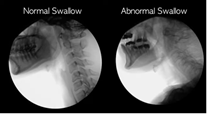

| Vai al video:Videofluoroscopia

della disfagia (Ianessa Humbert, 2020) |

video fluiroscopy: Ianessa Humbert. 8th May, 2020. Normal vs Abnormal

swallowing [Vídeo file].